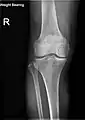

X-ray

- Knee X-ray

- Knee X-ray (weight bearing)

- Knee X-ray (weight bearing, flexion)